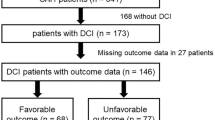

Any cerebral infarction occurred in 67 (46.9%) patients in the pre-implementation cohort and in 46 (29.1%) in the post-implementation cohort (aOR: 0.41 [0.24–0.69]). DCI-related cerebral infarction occurred in 45 (31.5%) patients in the pre-implementation cohort and in 28 (17.7%) patients in the post-implementation cohort, aOR was 0.41 [0.23–0.76] (Table 2, Figs. 3 and 5).

In the pre-implementation cohort, 77 (53.8%) patients had an unfavorable functional outcome versus 57 (37.3%) in the post-implementation cohort (aOR: 0.30 [0.17–0.54]) (Table 2, Figs. 4a and 5).

In patients who developed DCI, in the pre-implementation cohort, unfavorable outcome was present in 35 (77.8%) patients, compared to 52 (42.3%) patients in the post-implementation cohort (aOR: 0.1 [0.03–0.27]) (Table 2, Figs. 4b and 5).